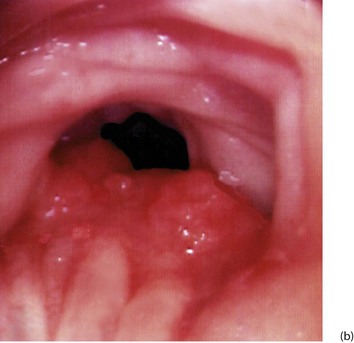

Fig. 27.1 Colorectal polyps

(a) This 65-year-old man was found to have positive faecal occult blood on colorectal cancer screening. This CT colography image shows a solitary polyp in the sigmoid colon, later removed by colonoscopic snaring. It proved to be a benign adenoma. (b) A 2 cm polyp on a long stalk in the sigmoid colon. (c) The snare loop is tightened around the stalk of the polyp before applying diathermy current to remove it and coagulate the blood vessels in the stalk. (d) Adenomatous polyp having mainly villous glandular architecture. The example shown has a well-defined stalk S, although this is more typical of tubular or tubulo-villous polyps, villous adenomas often having a broad base